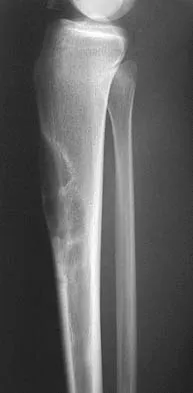

A 15-year-old boy reports leg pain after being tackled during football practice. Radiographs and a CT scan are shown in Figures 46a through 46c. The patient has a pathologic fracture through what underlying lesion?

Explanation

The images show a lobulated, eccentric, well-marginated lesion that is typical of a nonossifying fibroma. The lesion is slightly expansile, and the CT scan findings show that the lesion is very well marginated and the cortex is disrupted, which is a common finding. None of the characteristics of this lesion is aggressive in nature. Menendez LR (ed): Orthopaedic Knowledge Update: Musculoskeletal Tumors. Rosemont, IL, American Academy of Orthopaedic Surgeons, 2002, pp 69-75.